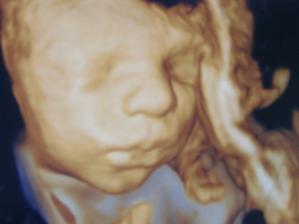

5.1.2012 - kontrola u doktorky, potvrdenie tehotenstva (5+6) - videla som malú krevetku

14.2.2012 - čaká nás sono, moc sa tešíme - sono nemohlo dopadnut lepšie. Som v 11+4 a malinke je 5,3 cm veľké, čo zodpovedá 12+0. Doktorka vravela, že plus mínus 2 dni je v poriadku.

17.2.2012 - ďalšie sono za nami. Toto bolo podrobné a trvalo 45 minút. Doktor všetko poukazoval, pomeral. Sme v poriadku a všetko je ako má byť. Som neskutočne šťastná....

10.4.2012 - sono v nemocnici - malinke robilo zle, kopalo do sona - pani doktorka nemohla male poriadne pomerat.... ale do tretice sa vsetko podarilo a sme v poriadku...

13.4.2012 - velke hodinove sono - babo pomerane (20 cm), zvazene (351 g) a teraz by sme kupovali topanocky 3,5 cm velke 🙂